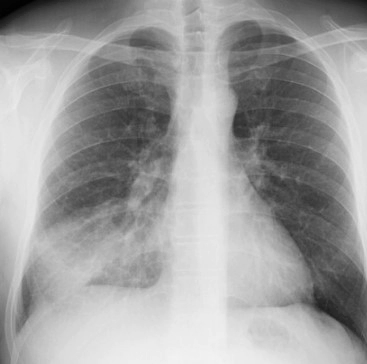

Q. 폐렴은 어떻게 진단되나요?

폐렴의 진단은 대체로 증상, 신체 진찰, 그리고 추가적인 검사를 통해 이루어집니다. 의사는 기침, 고열, 가슴 통증 등의 증상과 체온 측정, 심장 및 호흡 소리 청진 등의 신체 진찰을 진행할 것입니다. 또한, X-레이나 CT 스캔 같은 영상 진단, 혈액 검사, 가래 검사 등을 통해 확진을 내릴 수 있습니다.